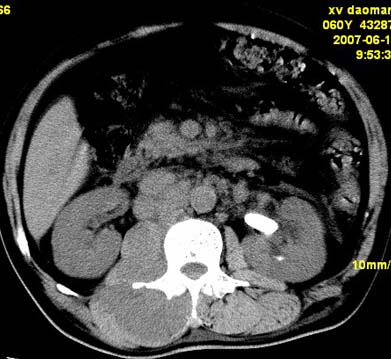

以下是引用还珠格格在2007-6-26 15:05:00的发言:[br]右侧腰大肌、同侧竖脊肌明显肿胀,呈不均匀密度减低影,右肾受压右上前移,脂肪间隙部分消失,另左侧肾盂内可见高密度影,是结石还是造影剂? 不知道病人用造影剂没有?考虑 右侧腰大肌及右侧竖脊肌寒性脓肿形成。[br][br][本贴已被 还珠格格 于 2007-6-26 15:21:35 修改过]

以下是引用小初学者在2007-6-26 15:42:00的发言:[br]1\\右侧腰大肌、同侧竖脊肌脓肿[br]2\\左侧肾盂结石

以下是引用刘明在2007-6-26 16:00:00的发言:[br][br]右侧竖直肌及腰大肌肿胀,脂肪间隙难辨,腹膜后血管旁见多个肿大淋巴结影,椎体附件右侧有压迫吸收、未见硬化迹象,考虑椎旁冷脓肿可能[br]左侧肾盂内可见高密度影,周围有毛刺,本图象是平扫,不是增强,应该是结石[br]